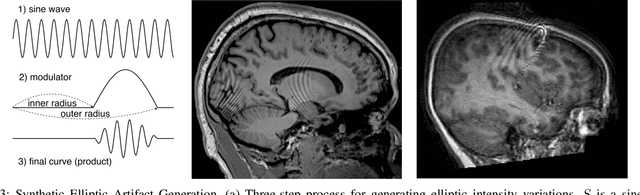

Abstract:In-scanner motion degrades the quality of magnetic resonance imaging (MRI) thereby reducing its utility in the detection of clinically relevant abnormalities. We introduce a deep learning-based MRI artifact reduction model (DMAR) to localize and correct head motion artifacts in brain MRI scans. Our approach integrates the latest advances in object detection and noise reduction in Computer Vision. Specifically, DMAR employs a two-stage approach: in the first, degraded regions are detected using the Single Shot Multibox Detector (SSD), and in the second, the artifacts within the found regions are reduced using a convolutional autoencoder (CAE). We further introduce a set of novel data augmentation techniques to address the high dimensionality of MRI images and the scarcity of available data. As a result, our model was trained on a large synthetic dataset of 217,000 images generated from six whole-brain T1-weighted MRI scans obtained from three subjects. DMAR produces convincing visual results when applied to both synthetic test images and 55 real-world motion-affected slices from 18 subjects from the multi-center Autism Brain Imaging Data Exchange study. Quantitatively, depending on the level of degradation, our model achieves a 14.3%-25.6% reduction in RMSE and a 1.38-2.68 dB gain in PSNR on a 5000-sample set of synthetic images. For real-world scans where the ground-truth is unavailable, our model produces a 3.65% reduction in regional standard deviations of image intensity.